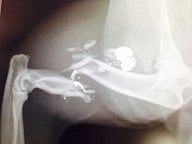

Alba was lucky that we found her when she was left abandoned behind bushes, weak, dehydrated and in severe, unnecessary pain. A quick x-ray at the veterinary clinic found a pellet and a very nasty fracture in a large area of the leg that contains nerves and blood vessels. A long surgical procedure took place to save Alba’s leg, which was an absolute challenge if we see the damage caused by the pellet’s impact.